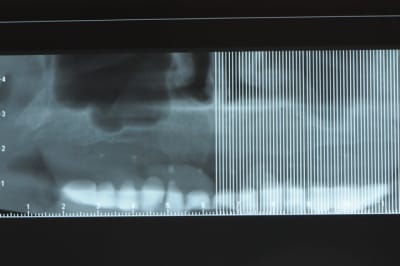

j'ai besoin de 4 implants au maxillaire pour faire tenir son complet.

dans la zone postérieur, pas de problème, mais devant, c'est une autre histoire.

avant de faire la tomosynthèse je comprenais pas pourquoi j'avais aussi peu de contraste.

le patient ne souhaite pas, ou ne peut pas se faire poser 6 implants en haut, donc...overdenture sur 4. (si possible)